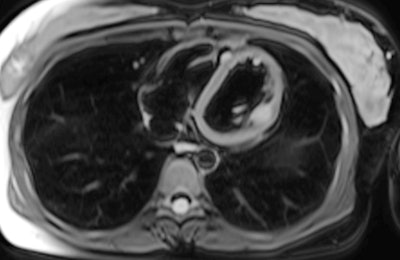

"Chest CT demonstrates poor sensitivity for detection of cardiac metastasis, with cardiac MRI performing much better. Still, neither CT nor MRI is as sensitive as [gallium-68 (Ga-68)] DOTATATE PET/CT for detection of neuroendocrine cardiac metastasis," noted Dr. John Renfrew and colleagues from the Mayo Clinic in Phoenix, Arizona, U.S.

The group evaluated the prevalence, distribution pattern, and radiotracer uptake characteristics of cardiac metastasis on Ga-68 DOTATATE PET/CT. On PET images, they documented and analyzed the maximum standardized uptake value of the cardiac metastasis and left ventricular chamber (blood pool), the Krenning score of the cardiac metastasis, and the presence of multisystem metastasis. They performed correlation with diagnostic CT and/or cardiac MRI to confirm the location of metastasis in the heart.

Five of the 26 patients also received a contemporaneous cardiac MRI. Four of these scans correctly identified cardiac neuroendocrine involvement.